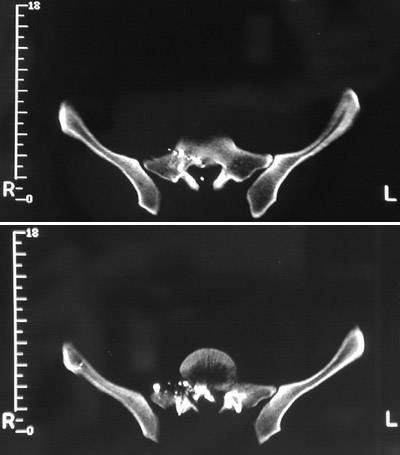

| The pelvic CT scan views above demonstrate a gunshot wound to the spine with bright bullet fragments and bone. A neurosurgical procedure was necessary to remove fragments from the spinal canal. In the view below, the density of the metal bullet scatters the x-rays ("beam hardening" artefact). |